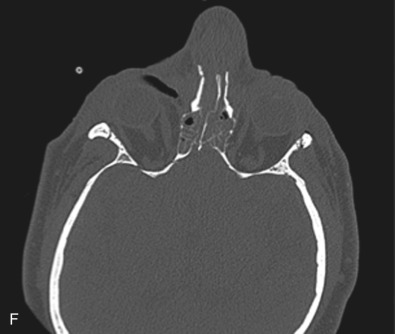

The gold standard for radiographic evaluation is thin-slice helical computed tomography (CT). Midface fractures are confirmed by axial, coronal, and sagittal views. The degree of comminution, bone loss, and detailed images of the fracture patterns can be assessed and juxtaposed to surrounding soft tissue structures. 3D reconstruction, when utilized, can aid in visualizing the complex 3D anatomical orientation of fracture fragments that occur in Le Fort injuries and facilitate reconstructive planning.

Le Fort I pattern fractures are characterized by a transverse fracture extending from the pyriform aperture, propagating laterally across the maxillary wall involving medial, anterior, and lateral components, and ending posteriorly at, or through, the level of the pterygoid plates ( Figs. 1.13.11–1.13.13 ). This results in mobilization of the lower third of the midface, whilst the upper two-thirds remains intact. The force is typically delivered above the maxillary teeth, causing a palatal/alveolar separation from the upper maxilla.